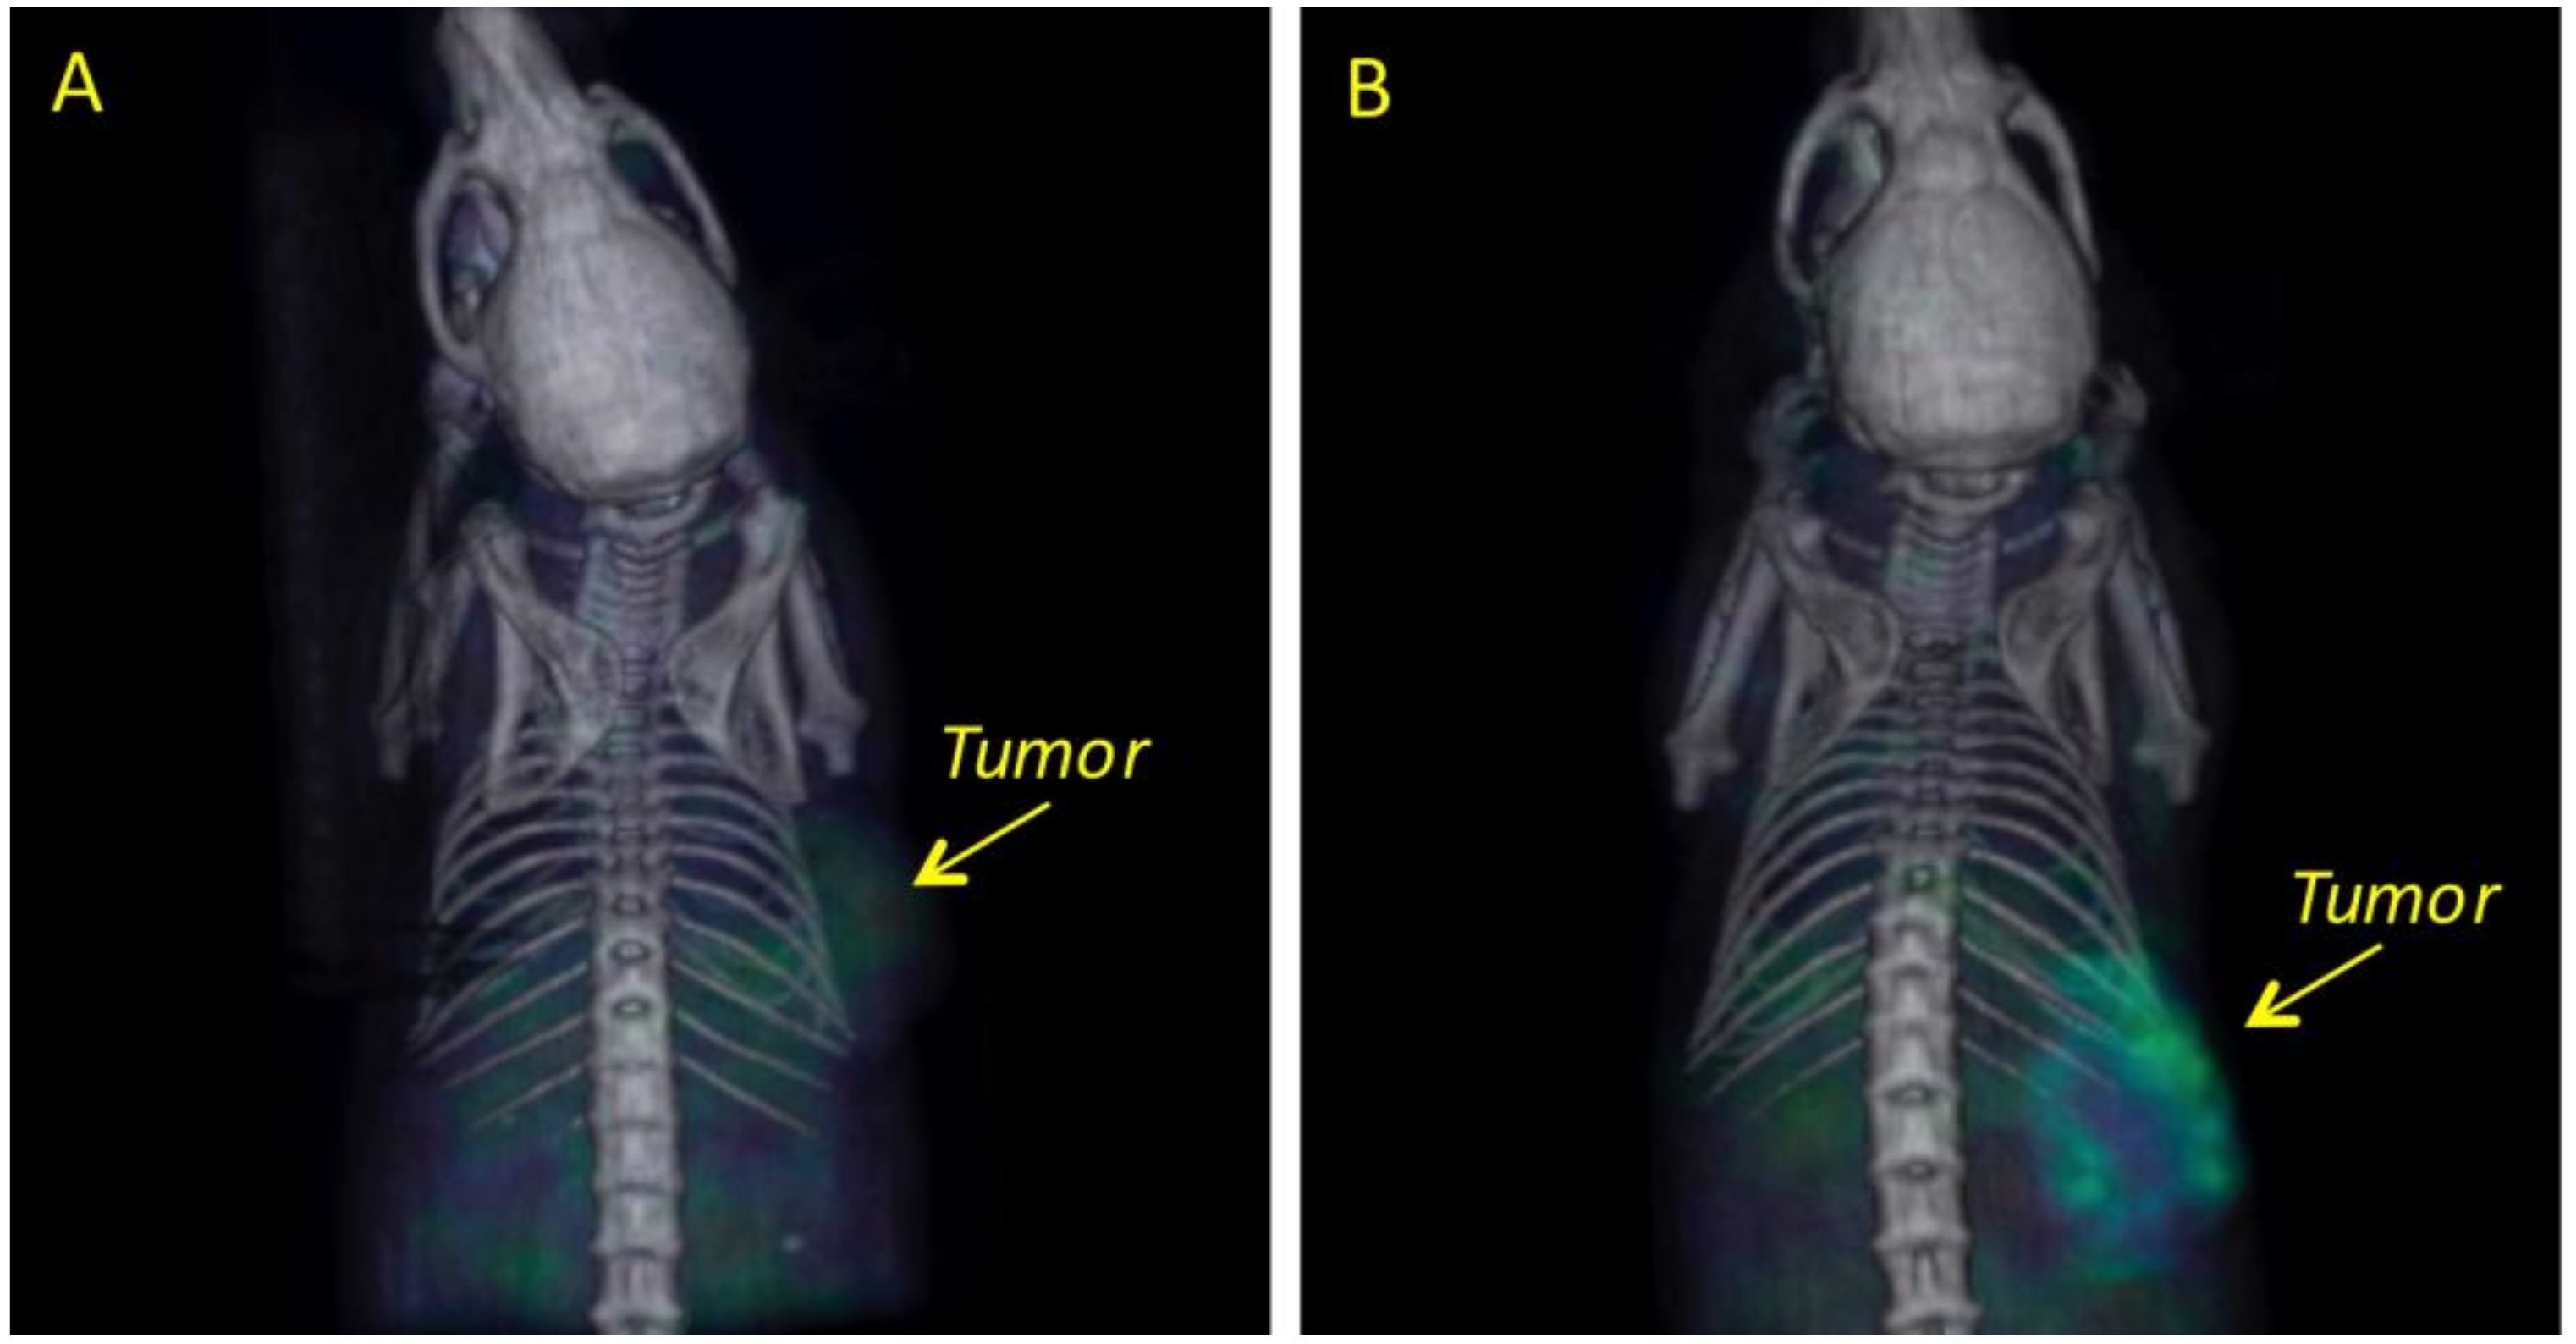

2.4. Biodistribution and Tumor Uptake in Mesothelioma Xenografts

4.8. Biodistribution and Molecular Imaging Studies